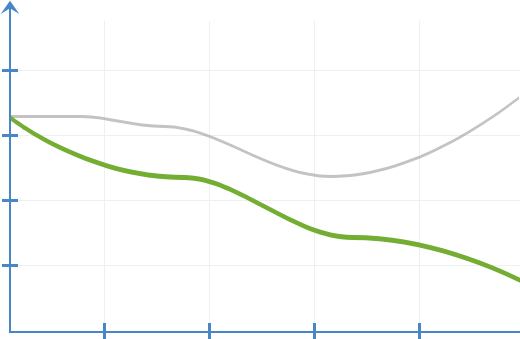

ცვლილებათა

დინამიკა

ანთებითი

პროცესების

დროს

Prostonix-ის გარეშე

Prostonix-ით